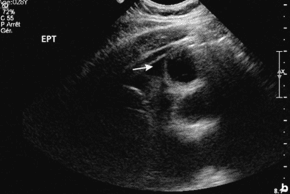

FIGURA  Ecografía de un apéndice normal (arriba) en la que se puede apreciar el espesor reducido de la pared en los planos frontal (izquierda) y longitudinal (derecha). En la apendicitis se produce una distensión y un aumento del espesor de la pared (abajo, derecha) y un aumento del flujo sanguíneo, lo que da lugar a lo que se conoce como imagen en anillo de fuego. A, apéndice.

Algunos autores han clasificado los  hallazgos ecográficos en:

Diagnóstico de certeza:

·      Estructura tubular no compresible de diámetro transverso > 6 mm.

·      Apendicolito con clínica sugestiva.

Diagnóstico probable:

·      Hiperecogenicidad de la grasa periapendicular.

·      Colección, flemón o absceso apendicular.

Diagnóstico poco probable:

·      Adenopatías peri apendiculares.

En general los signos positivos del diagnóstico ecográfico son una estructura tubular en fondo de saco de más de 6 mm de diámetro (Kaneko, 2004). Julien y Puylaert han descrito la técnica de la «compresión gradual», que permite la depresión progresiva de la fosa ilíaca derecha con la sonda de ecografía de manera que se visualice mejor el apéndice (Julien, 1986). Éste, cuando es patológico, es rígido y difícil de comprimir, con visualización a veces de un coprolito intraluminal no visible con el ASP, pues todavía no está calcificado. También se puede visualizar un derrame en la cavidad peritoneal periapendicular (absceso) o difuso (peritonitis), teniendo en cuenta que la ausencia de derrame no descarta en absoluto una peritonitis. Por tanto, la ecografía es una prueba a menudo fiable, que se puede repetir y con un coste moderado; debe utilizarse sin vacilar en caso de duda diagnóstica o en las niñas. Una de las limitaciones de esta prueba es la obesidad, debido a la mala ecogenicidad de la grasa.